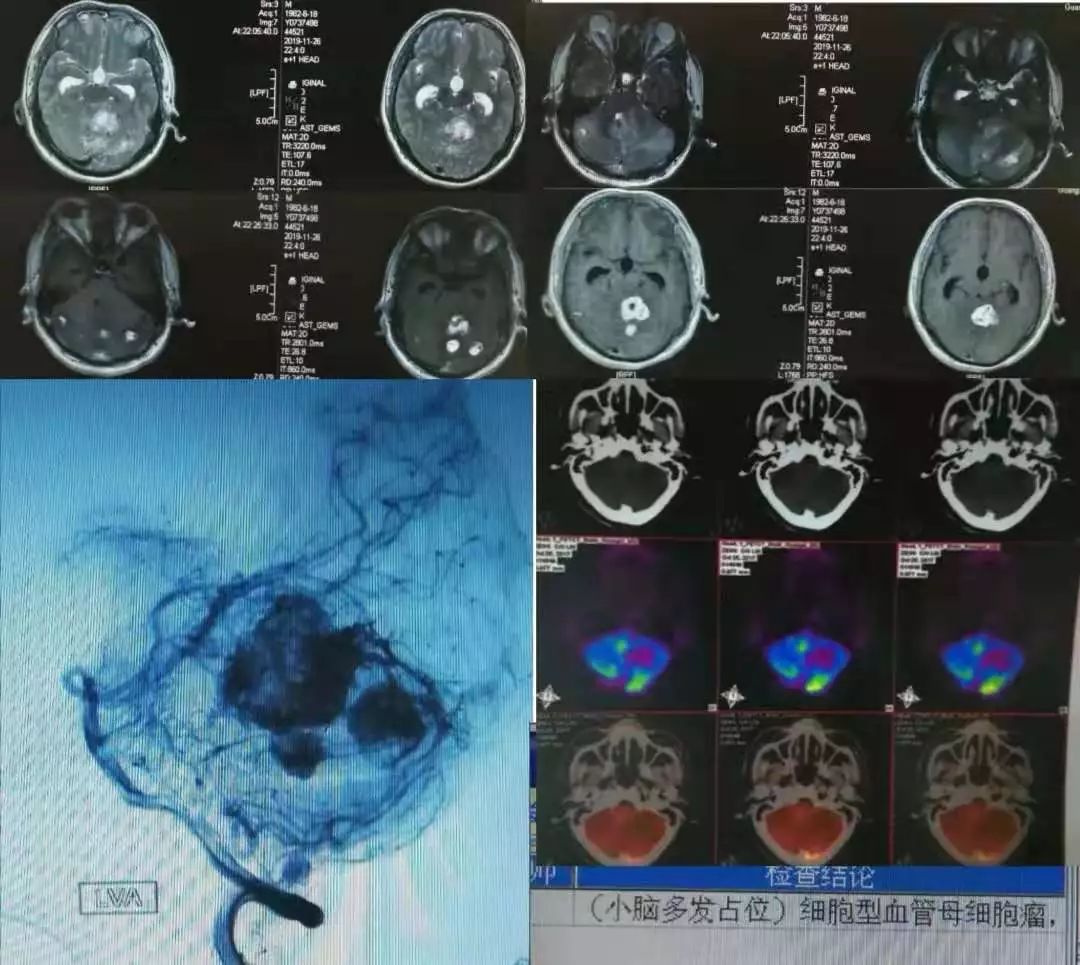

病例8

中年男性,突发言语不清。

诊断脑栓塞是没有问题的,重点在于栓子来源的筛查。对于病因,群里老师们的总结已经很有一套;对于这个患者,却画风突变,1年后癫痫发作再次入院,颅脑影像如下:

答案:心脏黏液瘤。

近期群内发过一个手术切除后的心脏黏液瘤标本视频,直观生动印象深刻。心脏黏液瘤是最常见的原发性心脏肿瘤,占原发性心脏肿瘤的 50% 以上,70%发生在左心房。心脏黏液瘤具有良性特征,但因其质脆易碎易脱落进入血液循环并转移至全身其他部位,产生不良后果,心脏黏液瘤可具有以下3种心脏外转移的病理学过程:脑血管梗死引起缺血性卒中,实质性肿瘤定植、转移和肿瘤性多发性脑动脉瘤形成、伴或不伴出血。

1894年Marchand首次报道心脏黏液瘤导致多发性颅内动脉瘤形成,它是心脏黏液瘤的中枢神经系统并发症之一。心脏黏液瘤导致多发性颅内动脉瘤形成的可能机制有:(1)血管损伤理论:心脏黏液瘤细胞栓子脱落,经体循环进入脑血管,脑动脉末梢管腔直径小,瘤栓附着于微小动脉壁上,导致血管内皮损伤、瘢痕形成,引起颅内动脉瘤形成;(2)肿瘤定植理论:肿瘤细胞进入脑血管系统后,仍可以保持活力并在局部定植生长。肿瘤组织破坏血管壁,甚至血管壁整个基层均被肿瘤组织破坏、替代,这样可使得其在造影时不仅像真的动脉瘤一样呈瘤样扩张,还有造影剂明显滞留的表现。定植在脑血管内壁的肿瘤细胞有不同的生物学行为,不同的生长速度、方式,既可处于生长休眠状态也可最终坏死,这就可以解释迟发性病变以及多样的动脉瘤形态。在以上两种假说中,脑梗死事件都会发生。而多数学者赞同肿瘤定植理论,有文献报道在组织病理学研究中已经证明了动脉瘤壁中含有活性黏液瘤细胞的增殖及其对内弹力层的侵袭破坏。